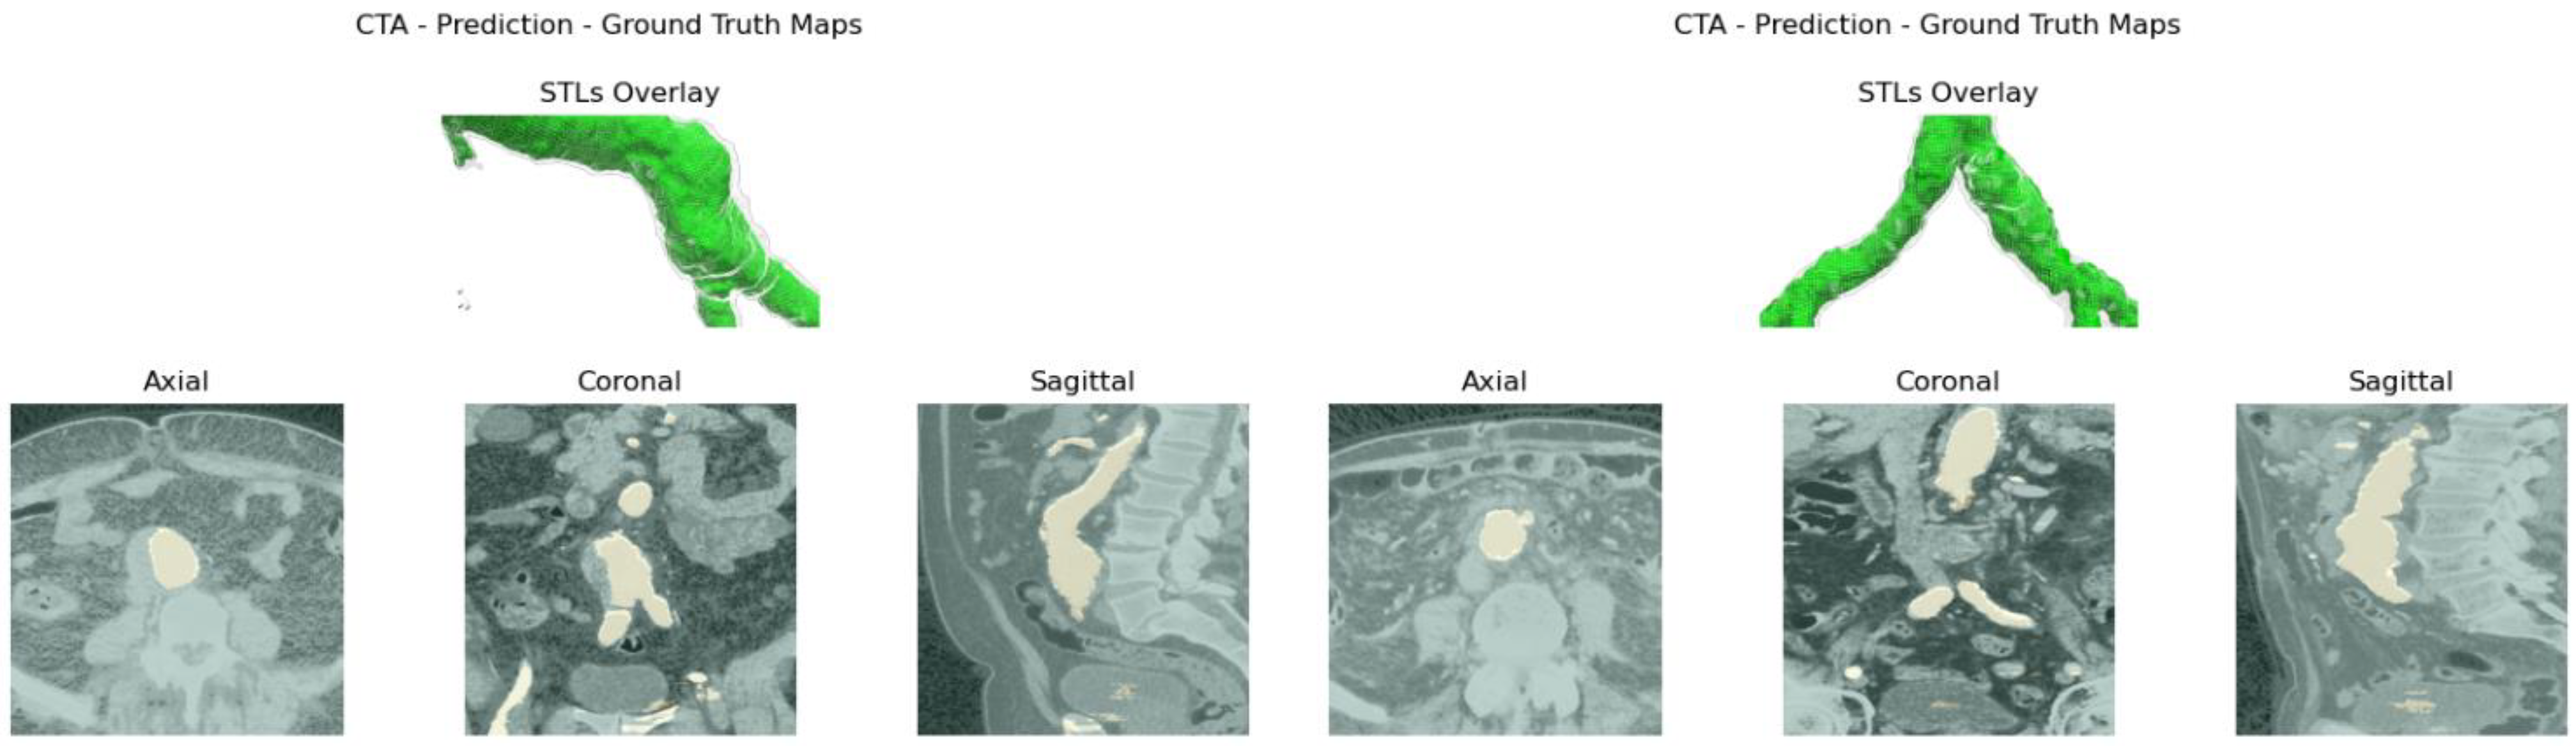

Case ID_3 shows the best metrics among the other patients, respectively, achieving an IoU = 0.850 ± 0.087 and an F1 = 0.916 ± 0.053 average values over each ROI perturbation. The superior mesenteric artery has been detected successfully, including the tripod. Common iliac arteries and aneurysmatic sections are also segmented correctly as well as the right common iliac PAU, as shown in Figure 5a.

Case ID_2, representing the average U-Net performance, reported an IoU = 0.810 ± 0.088 and an F1 = 0.892 ± 0.055 over each ROI’s orientation. The LIIO of such a vessel has been successfully detected. Moreover, the common iliac section and the superior mesenteric artery were also identified and reconstructed successfully, as can be seen from Figure 5b.

Case ID_12 represents the worst performance scenario, reporting an IoU = 0.752 ± 0.153 and an F1 = 0.847 ± 0.126 over each ROI’s orientation. The network provided solid and reliable results despite lower average metrics’ value and a higher standard deviation across slices. The 3D reconstruction for case ID_12 is reported in Figure 5c.

Figure 5. U-Net (in blue) and ITK-Snap (in green) 3D surfaces of the aortic lumen: cases ID_3 (a), ID_2 (b) and ID_12 (c).